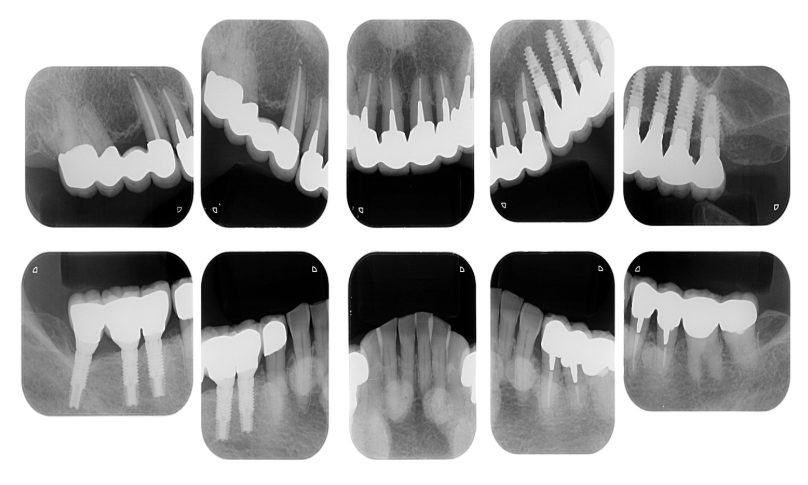

| 治療内容 | 歯周病で骨の吸収が重度で保存不能なため抜歯、仮の入れ歯を作り、6ヶ月の抜歯窩の治療の後に、インプラントのCTによる診査診断を行い、下顎に6本インプラント埋入と同時に仮歯を入れる。その後、上顎は8本のインプラント埋入と同時に仮歯を入れる。左右上6はソケットリフトによる上顎洞拳上術を行う。その後免荷期間6ヶ月待ってセラミックを用いた上部構造作製、装着しメンテナンスに移行する。 |